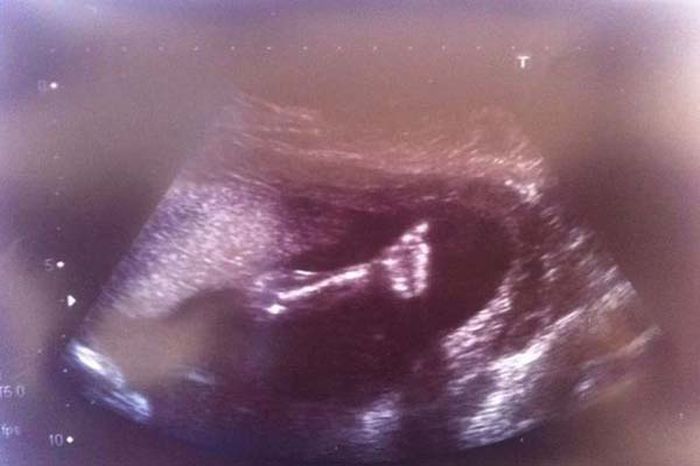

Когда на 20-ой неделе беременности маме малышки Фэй сказали, что у ребёнка обнаружен синдром гипоплазии левых отделов сердца- состояние, при котором только одна сторона сердца может биться правильно, ей предложили прервать беременность. Шансы на то, что ребёнок сможет выжить были ничтожно малы, но Фэй и ее муж Майкл были полны решимости довести дело до конца, как только будущая мама почувствовала, что Шанель бьёт ножками в её утробе, а на УЗИ будущие родители увидели поднятый вверх палец малышки.